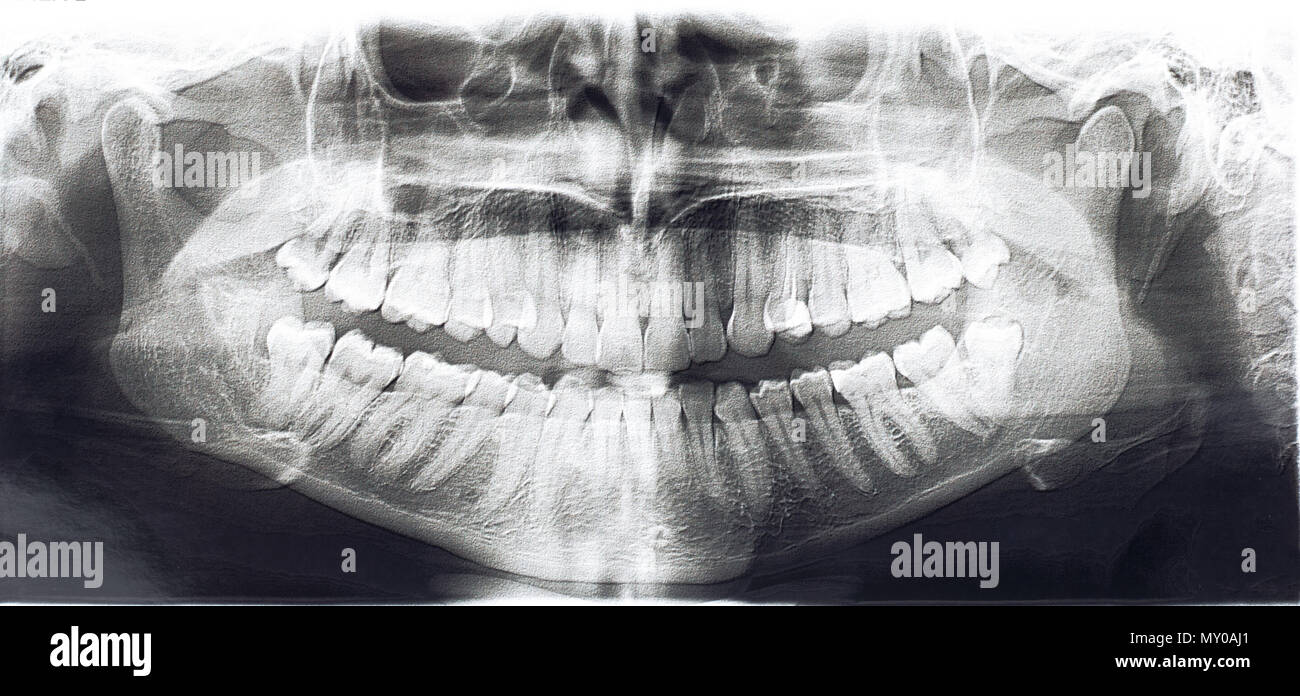

From www.alamy.com

front view of human jaws on Xray image Stock Photo Alamy Jaw X Ray Views The temporomandibular joint (tmj) is an atypical synovial joint located between the condylar process of the mandible and the mandibular. Proper characterization of jaw abnormalities is essential to ensure appropriate patient care and reduce morbidity. This projection is useful in identifying structural changes and displaced fractures of the mandible in a trauma setting, and in neoplastic or inflammatory changes. The. Jaw X Ray Views.